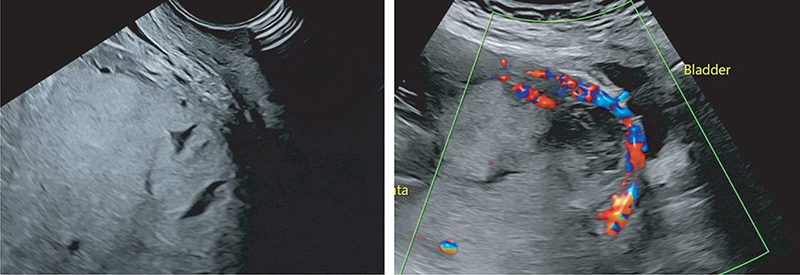

The most common ultrasound findings in the true positive cases were myometrial thinning (12/12 cases), loss of the placental basal plate (11/12 cases), loss of the sub-placental ‘clear zone’ (11/12 cases), and placental lacunae (10/12 cases) (Figs. 1 and 2). The presence of an exophytic mass was the only sign not observed in either true or false positive cases.

JOGM-5-331-F2.jpg

Fig. 2. Placenta percreta with cervical involvement. Left – diffuse placental lacunae, absent myometrium. Right – distortion of the cervix with associated hypervascularity.

Bladder line disruption and a bladder ‘bulge’ had the highest positive predictive value (PPV) of any sonographic PAS sign (100% PPV in each); however, these signs were present only in a small number of cases (identified in 1/12 and 5/12 of the true positive cases, respectively and not seen in any of the false positive cases). There were, however, no cases of uterine dehiscence in the false positive group, and it should be noted that both bladder line disruption and bladder ‘bulge’ have been reported in cases of uterine dehiscence without PAS.

Subplacental hypervascularity and the presence of placental lacunae demonstrated the lowest PPVs for the sonographic PAS signs (53 and 56% PPV, respectively). Subplacental hypervascularity was observed in seven of eight false-positive cases, compared to 11 of 12 true-positive cases. Placental lacunae were also seen in seven of eight false-positive cases, compared to 10 of 12 true-positive cases.